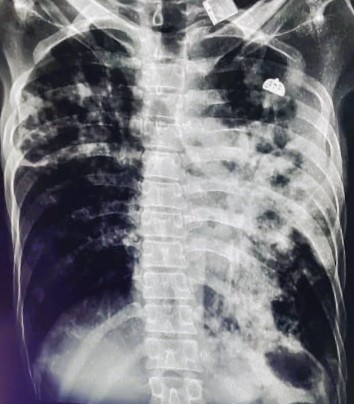

| 318 | IGGMC, Nagpur, Nagpur | P2 | 29-4154 | Tahera Bee | Consent taken on Paper | 70 Yrs. |

Provisional Diag : Post TB Bilateral Bronchiectasis

Final Diag : Post TB sequalae, Bilateral Bronchiectasis In Lower Lobe With Type 1 Respi Failure With Sepsis With Septic Shock With SYST HTN |

Post TB Sequelae | Abnormality visible on x-ray |